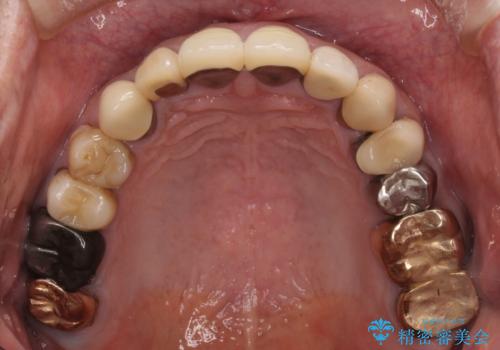

奥歯1歯分を動かすには時間がかかるため、矯正治療には思いの外時間がかかりました。

痛みのある奥歯は必要に応じて根管治療を行い、左下インプラントは角化歯肉の移植により清掃性を向上させ、気になっていた部分をしっかりと改善させることができました。